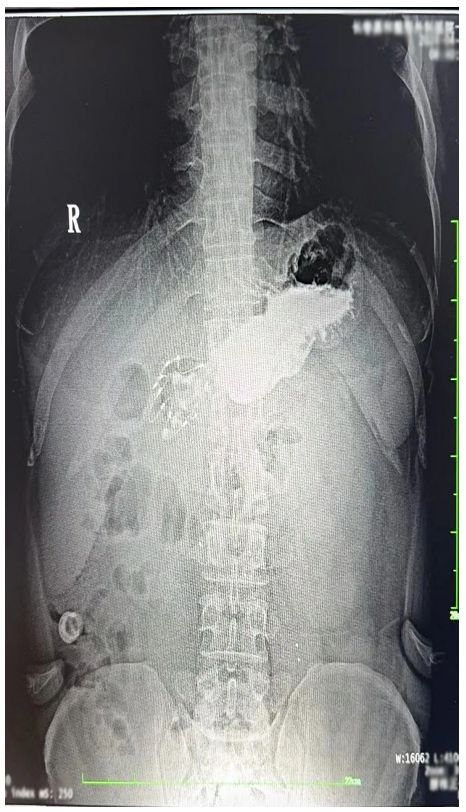

術(shù)后的觀察期,我感覺胃部有些異物感,但在可忍受的范圍。于是靜滴結(jié)束后,我就回家了。路途中輕微顛簸加重了胃部的不適感,通過平臥休息后不適感逐漸緩解。次日清晨,我感覺麻醉的影響基本消失,身體恢復(fù)如常。為了確認(rèn)支架置入的情況,我在醫(yī)院復(fù)查了上消化道造影,造影顯示支架系統(tǒng)順利展開,位置正確。這一刻,我心中懸著的石頭落地,隨即我便投入到工作中(特別說明:此行為基于個人職業(yè)的特殊性,我建議普通患者術(shù)后還是要充分休息)。

上消化道造影照片上消化道造影照片